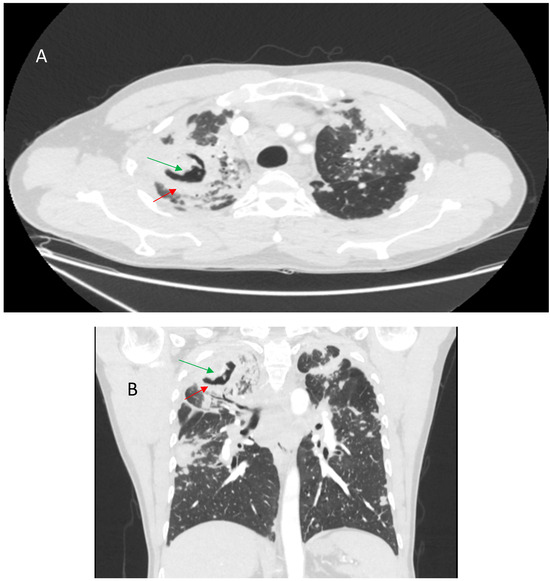

Sarcoidosis is a chronic, idiopathic, multisystemic inflammatory disease characterized by non-caseating granulomas, most commonly affecting the lungs and mediastinal lymph nodes. Radiological imaging plays a fundamental role in the diagnosis, assessment of disease extent, and differentiation from other pulmonary conditions. This narrative review [...] Read more.

Sarcoidosis is a chronic, idiopathic, multisystemic inflammatory disease characterized by non-caseating granulomas, most commonly affecting the lungs and mediastinal lymph nodes. Radiological imaging plays a fundamental role in the diagnosis, assessment of disease extent, and differentiation from other pulmonary conditions. This narrative review offers a comprehensive overview of the imaging features of pulmonary sarcoidosis, focusing on both typical patterns—such as bilateral hilar lymphadenopathy, perilymphatic nodules, and upper lobe-predominant infiltrates—and atypical manifestations—including alveolar opacities, miliary nodules, fibrocystic changes, and lower lobe involvement. Emphasis is placed on the utility of high-resolution computed tomography (HRCT) in detecting early parenchymal changes and complications such as fibrosis, bronchiectasis, and pulmonary hypertension. Differential diagnosis, including tuberculosis, silicosis, metastatic disease, organizing pneumonia, and hypersensitivity pneumonitis, are discussed to aid interpretation. Recognizing the spectrum of radiological presentations is essential for distinguishing sarcoidosis from other interstitial and granulomatous lung diseases. Radiologists play a pivotal role in the multidisciplinary diagnostic process, contributing to timely diagnosis, risk stratification, and optimized patient management. Full article

Figure 1